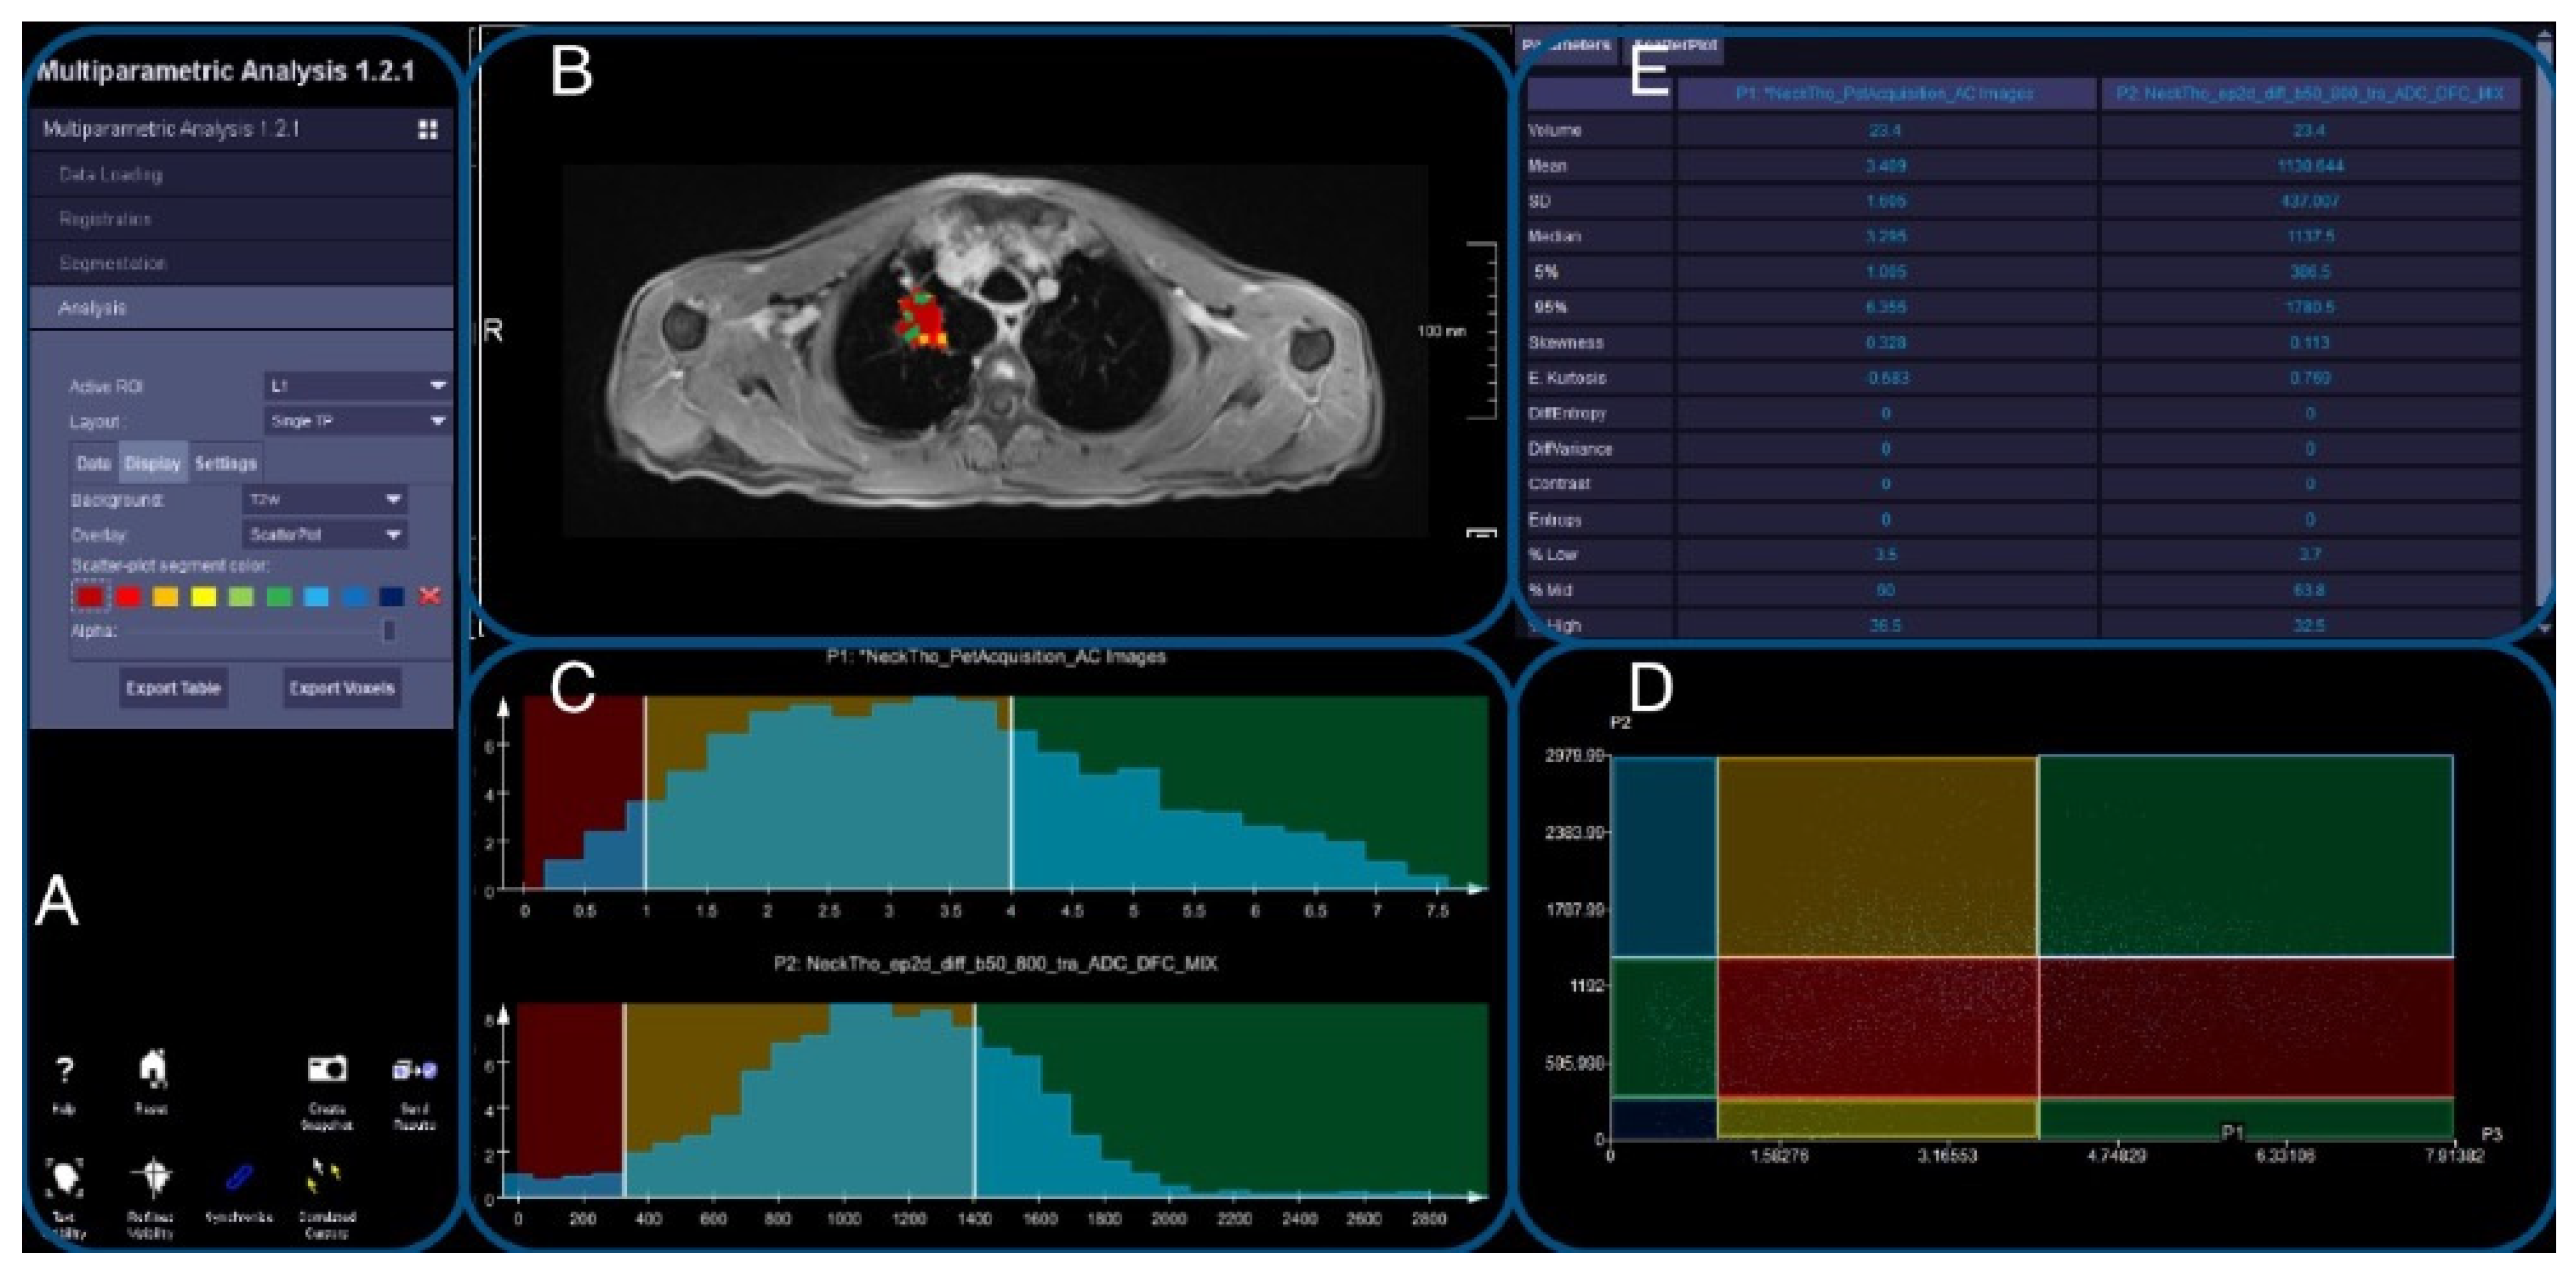

2.8. Image Evaluation

2.9. DWI and PET Registration

2.10. Evaluation of Registered Datasets

3.4. Thoracic Tumor Segmentation and Registration

3.5. Plausibility of DWI and PET Images